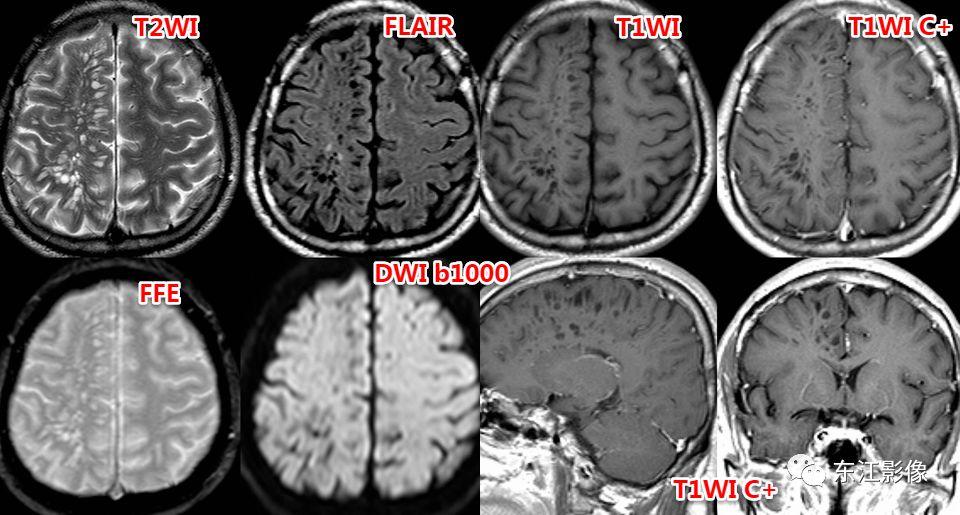

5. 脑脊液流动伪影

- 脑脊液流动伪影主要见于T2WI、FLAIR,主要是长TE序列容易出现流空效应的缘故。

- 但由于脑脊液流动方向、速率不一等因素的影响,呈现为非脑脊液信号影像,部分呈囊样。

- 常见于第三脑室、侧脑室室间孔旁区、脑干周围脑池(这些区域结构复杂)。

- 鉴别要点,T1WI、增强未能辨认;DWI与邻近一致的无信号;无占位效应。

侧脑室室间孔旁脑脊液流动伪影。

又一例。

桥前池脑脊液流动伪影。